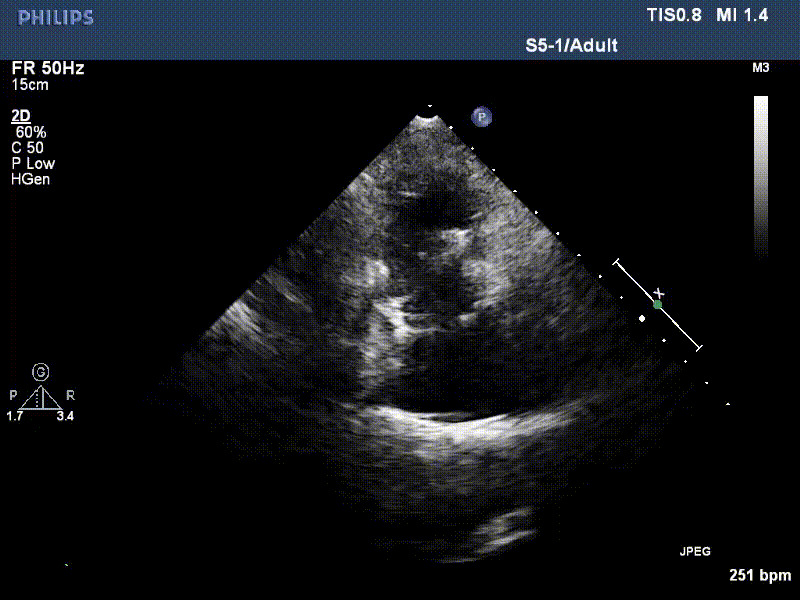

流并分別伴有房顫和房撲,高外科手術(shù)風(fēng)險。術(shù)前超聲提示,兩例患者下腔靜脈寬度分別為13mm和29mm,右房內(nèi)徑(上下徑和左右徑)分別為52×41mm和53×43mm,彩色多普勒顯示極重度三尖瓣反流,VCW分別為14×15mm和10mm。

1年前,兩例患者因難治性雙下肢水腫輾轉(zhuǎn)多家醫(yī)院尋求救治,考慮到兩例患者高齡、基礎(chǔ)疾病多、STS評分高,不適合傳統(tǒng)外科開胸手術(shù),葛均波院士及其團隊周達新教授、潘文志教授、張源博士、陳莎莎博士、陳丹丹博士聯(lián)合心外科王春生、魏來主任,麻醉科繆長虹、郭克芳主任以及心超室的潘翠珍教授、李偉教授共同討論決定,采用我國創(chuàng)新器械LuX-Valve Plus經(jīng)血管三尖瓣置換系統(tǒng)為患者進行手術(shù)。相較于第一代產(chǎn)品LuX-Valve,LuX-Valve Plus經(jīng)血管三尖瓣置換系統(tǒng)對輸送系統(tǒng)進行了全面升級,實現(xiàn)了經(jīng)頸靜脈入路的方式,進一步減小了手術(shù)風(fēng)險和對患者的創(chuàng)傷。目前隨訪1年心超結(jié)果顯示,三尖瓣極重度反流消失,人工三尖瓣瓣膜穩(wěn)定牢固,瓣葉活動度良好,右心室及下腔靜脈明顯縮小,心輸出量增加。兩位老人手術(shù)后沒有出現(xiàn)過胸悶氣促的癥狀,下肢水腫緩解,活動耐力提升,生活質(zhì)量也大為提高。

圖2 患者植入LuX-Valve Plus后,1年隨訪心超提示無三尖瓣反流